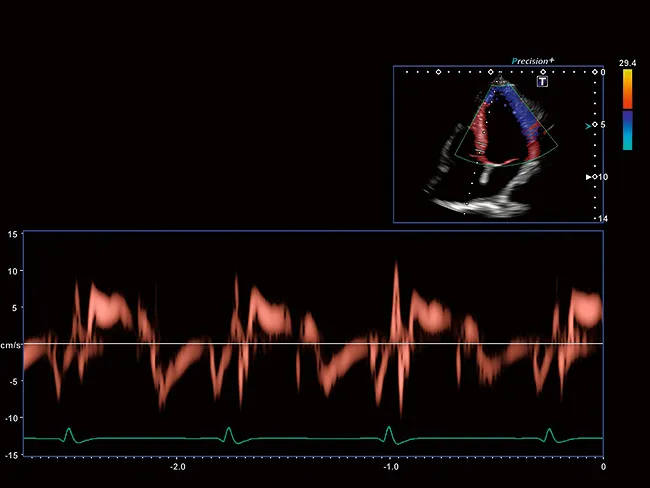

Aplio обеспечивает цветную допплерографию с превосходным пространственным разрешением, позволяющую выявлять мельчайшие узоры кровотока с беспрецедентной точностью и детализацией при высокой частоте кадров, сохраняя при этом полное качество изображения в режиме B

Aplio предоставляет вам тканевые допплеровские изображения с высокой частотой кадров и импульсно-волновые TDI-треки для точного определения времени сердечнолго ритма как в визуальном, так и в количественном формате.